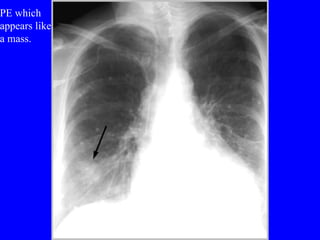

Pulmonary embolism (PE) is a common and potentially fatal condition where blood clots block arteries in the lungs. An estimated 5 million venous thromboses occur annually worldwide, with 10-30% of cases resulting in PE. Risk factors include immobilization, surgery, cancer, and estrogen use. Diagnosis involves assessing clinical probability based on symptoms and risk factors, followed by tests like D-dimer, chest imaging, ultrasound, V/Q scan, CT, or angiogram. Treatment aims to prevent further clotting with anticoagulants like heparin and warfarin, provide supportive care, and in some severe cases utilize thrombolysis or embolectomy.